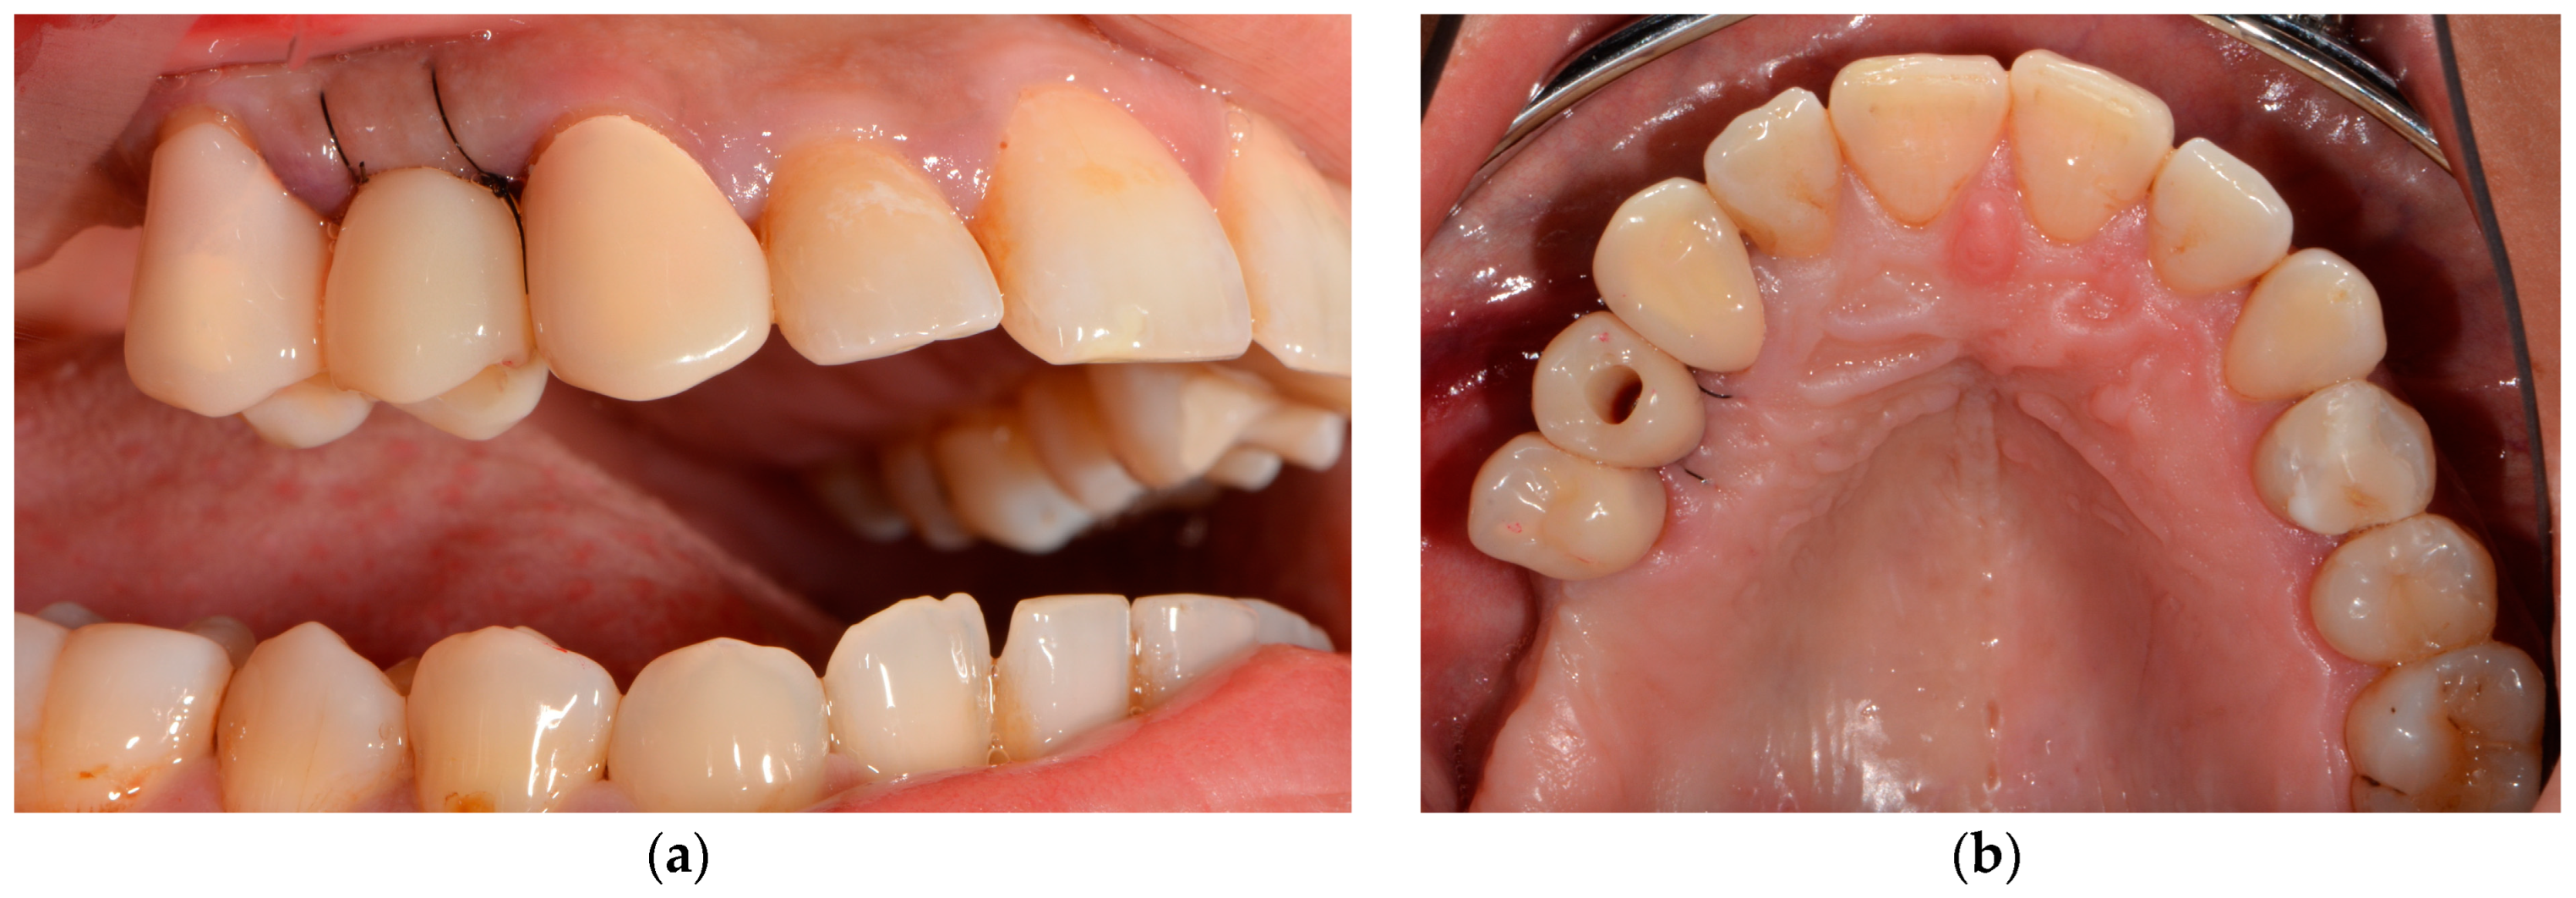

4. Surgical Procedures

| Surgical | Computer-assisted implant surgery |

| Restorative | Intraoral scans with a scanbody |

| Chairside, computer-aided design and milling of the provisionalization | |

| Placement of the chairside LTT |